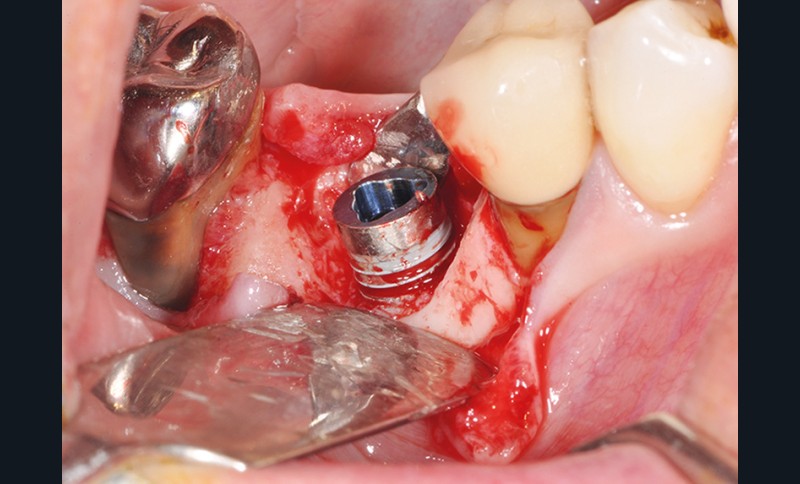

La stabilité des tissus mous autour des implants apparaît également comme un facteur très déterminant. L’absence de barrière kératinisée stable crée une mobilisation haute des tissus jusqu’au col implantaire. Cela a pour conséquence l’apparition de déhiscence gingivale, puis la disparition de l’os vestibulaire ou lingual.

La surface implantaire, ainsi exposée, fait office de porte d’entrée bactérienne. L’état de surface et sa capacité à fixer plus ou moins facilement les bactéries jouent alors un rôle primordial dans l’évolution de la pathologie.

Ce sujet est depuis de nombreuses années discuté et étudié dans le monde de l’implantologie. Il est évident que certaines surfaces présentent, soit par leur mode d’obtention, soit par leur niveau de rugosité, davantage de risques.